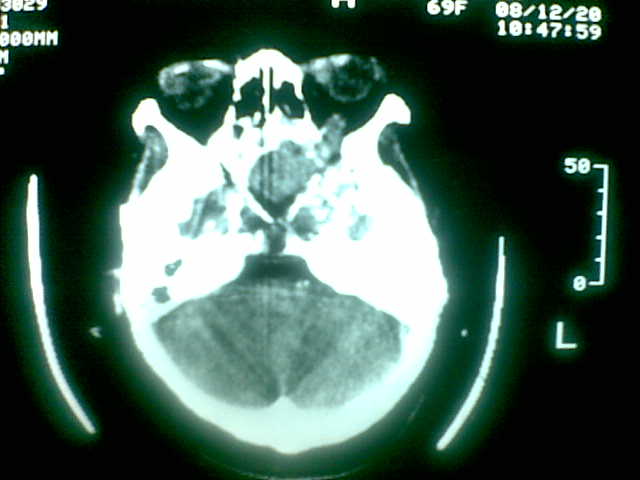

69岁 女 主因头痛就诊。大家看看起源于哪里啊

起源于斜坡,考虑脊索瘤.

起源于斜坡,考虑脊索瘤. 很典型

考虑脊索瘤(起源于蝶枕联合部)。

颅底骨质破坏伴软组织密度影、斑片状高密度(死骨影)。

考虑:脊索瘤。

多为脊索瘤。起源于斜坡!